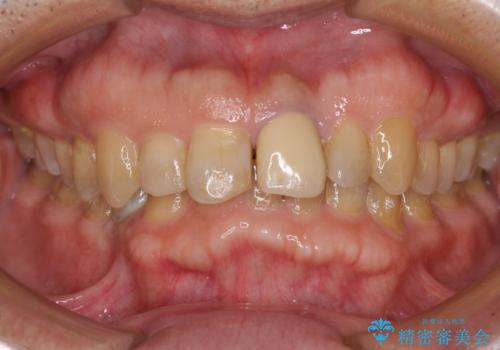

インビザラインによる治療を希望されたため、左側のスペースは閉じ、右側はスペースをより拡大し、インプラント補綴を行うこととしました。

咬合力が強く、インビザラインのみではディープバイトを改善することができず、半年間ほどワイヤー装置による矯正治療を行いました。

インプラントの埋入は矯正治療中に行い、矯正治療後はインプラント上補綴および、前歯のセラミック治療を行いました。